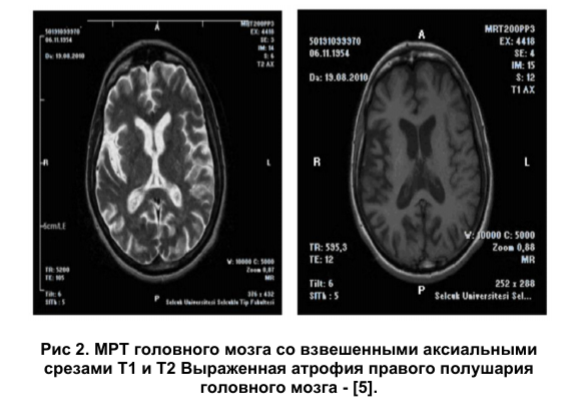

Клинических рекомендаций по диагностике и лечению СМ в настоящее время не разработано. На сегодняшний день лабораторные маркеры этой патологии неизвестны, поэтому диагностика СМ основывается на анализе клинической картины и характера прогрессирования заболевания. Применяемые нейровизуализационные методы (компьютерная томография, магнитно-резонансная томография, магнитно-резонансная трактография) лишь подтверждают диагноз. Выявляется асимметричный локальный атрофический процесс, который затрагивает моторную кору и/или пирамидный путь (рис.1, 2, 3).